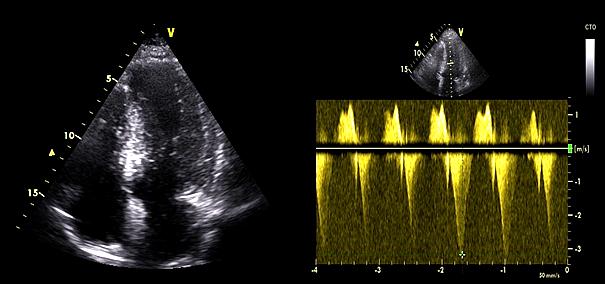

Comprehensive baseline and follow-up data, including demographic, clinical, and echocardiographic measurements, were collected retrospectively from the hospital’s electronic records, allowing for a detailed analysis of patient profiles and procedural outcomes within a defined cohort. Computed tomography (CT) imaging evaluated midventricular thickness, offering detailed anatomical visualization of the hypertrophied segment (Figure 2). This modality complemented transthoracic echocardiography (TTE) in assessing the severity and extent of MVO. Cardiac magnetic resonance imaging (MRI) was conducted to further evaluate the hypertrophied midventricular segment in short-axis and 4-chamber views (Figure 3). This advanced imaging technique provided detailed anatomical visualization and was especially useful in cases needing further clarification (including the presence of fibrosis) beyond echocardiographic and CT evaluation findings.